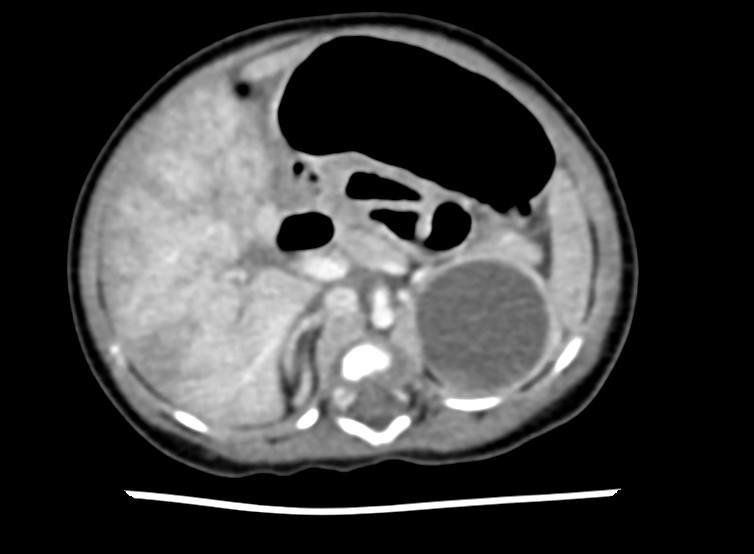

面对紧急情况,襄阳市第一人民医院迅速启动应急预案,召集心胸外科急诊科麻醉科输血科等多学科团队进行联合会诊。经过研判和检查,专家们确认卢先生患有主动脉夹层(Standford A型),且主动脉夹层撕裂已累及根部,卢先生还合并有急性心梗,随时都有破裂大出血的风险。

在手术过程中,王志维教授发现患者的心脏增大,心包腔内存在大量血性心包积液,升主动脉外膜呈现青紫色,升主动脉及主动脉弓部瘤样扩张。由于患者过于肥胖,血氧饱和度低,此外,患者术前曾大量使用抗凝药物,导致术中止血变得异常困难,这无疑为手术增添了额外的难度和风险。